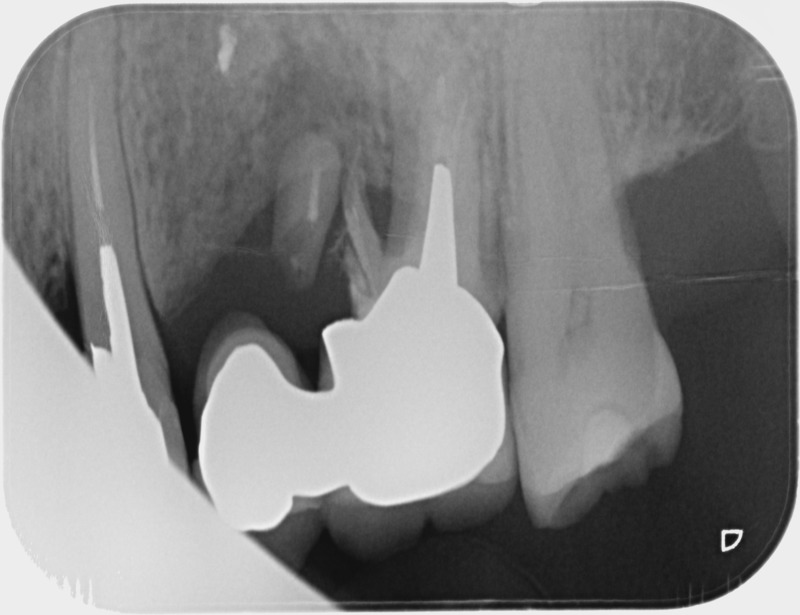

• Couronnes sur implants : Lorsqu’un implant est posé en remplacement des racines d’une dent, il est conçu pour recevoir d’abord un pilier vissé puis une couronne céramique. Le couple couronne - implant se substitue à la dent manquante pour en assurer les mêmes fonctions. Nous pouvons également adapter un bridge sur plusieurs implants dans le cas d’un édentement plus important.

Après